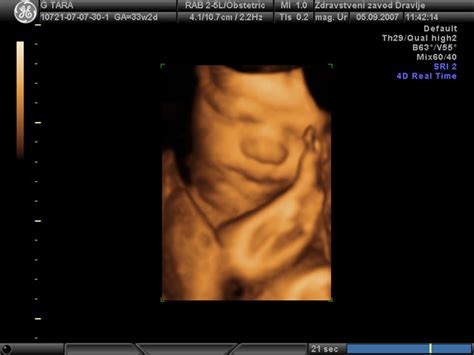

- Redni pregledi: Bodite pozorne na redne preglede pri ginekologu, ki vključujejo spremljanje stanja ploda (CTG, ultrazvok, merjenje pretokov skozi plodovnico) in nosečnice.